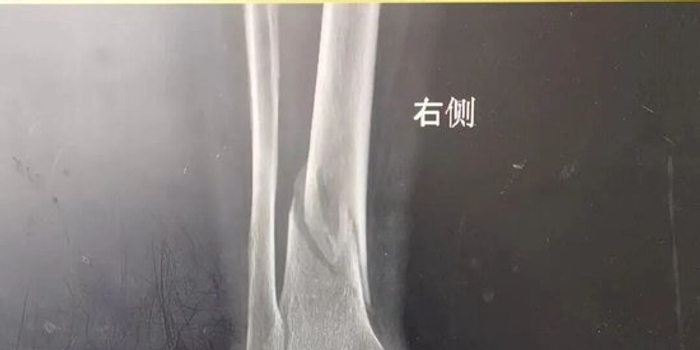

69岁的相女士因意外摔伤导致左下肢剧烈疼痛、无法活动,被紧急送至平原县人民医院急诊科,医护人员第一时间开启绿色通道,迅速完成初步检查,检查发现患者左下肢肿胀、左足感觉减退,情况紧急,迅速通知关节(运动医学)外科会诊。科室主任杜明火速赶到现场,面对患者有关节置换史的棘手情况,他带领团队谨慎评估,最终制定了周密的手术方案,并在与家属深入沟通后,确定了右侧胫腓骨骨折切开复位内固定术的治疗方案。

手术由杜明主任主刀,倪守洋、冯志强医师协助进行。在硬膜外麻醉后,团队经患者右侧小腿切口,精准清除病灶,明确为胫骨远端螺旋型骨折。术中,团队顺利复位骨折端,先以3枚克氏针临时固定;在透视确认对位良好后,再置入胫骨远端钛板与皮质骨螺钉,实现牢固固定。整个过程顺利,患者生命体征平稳。